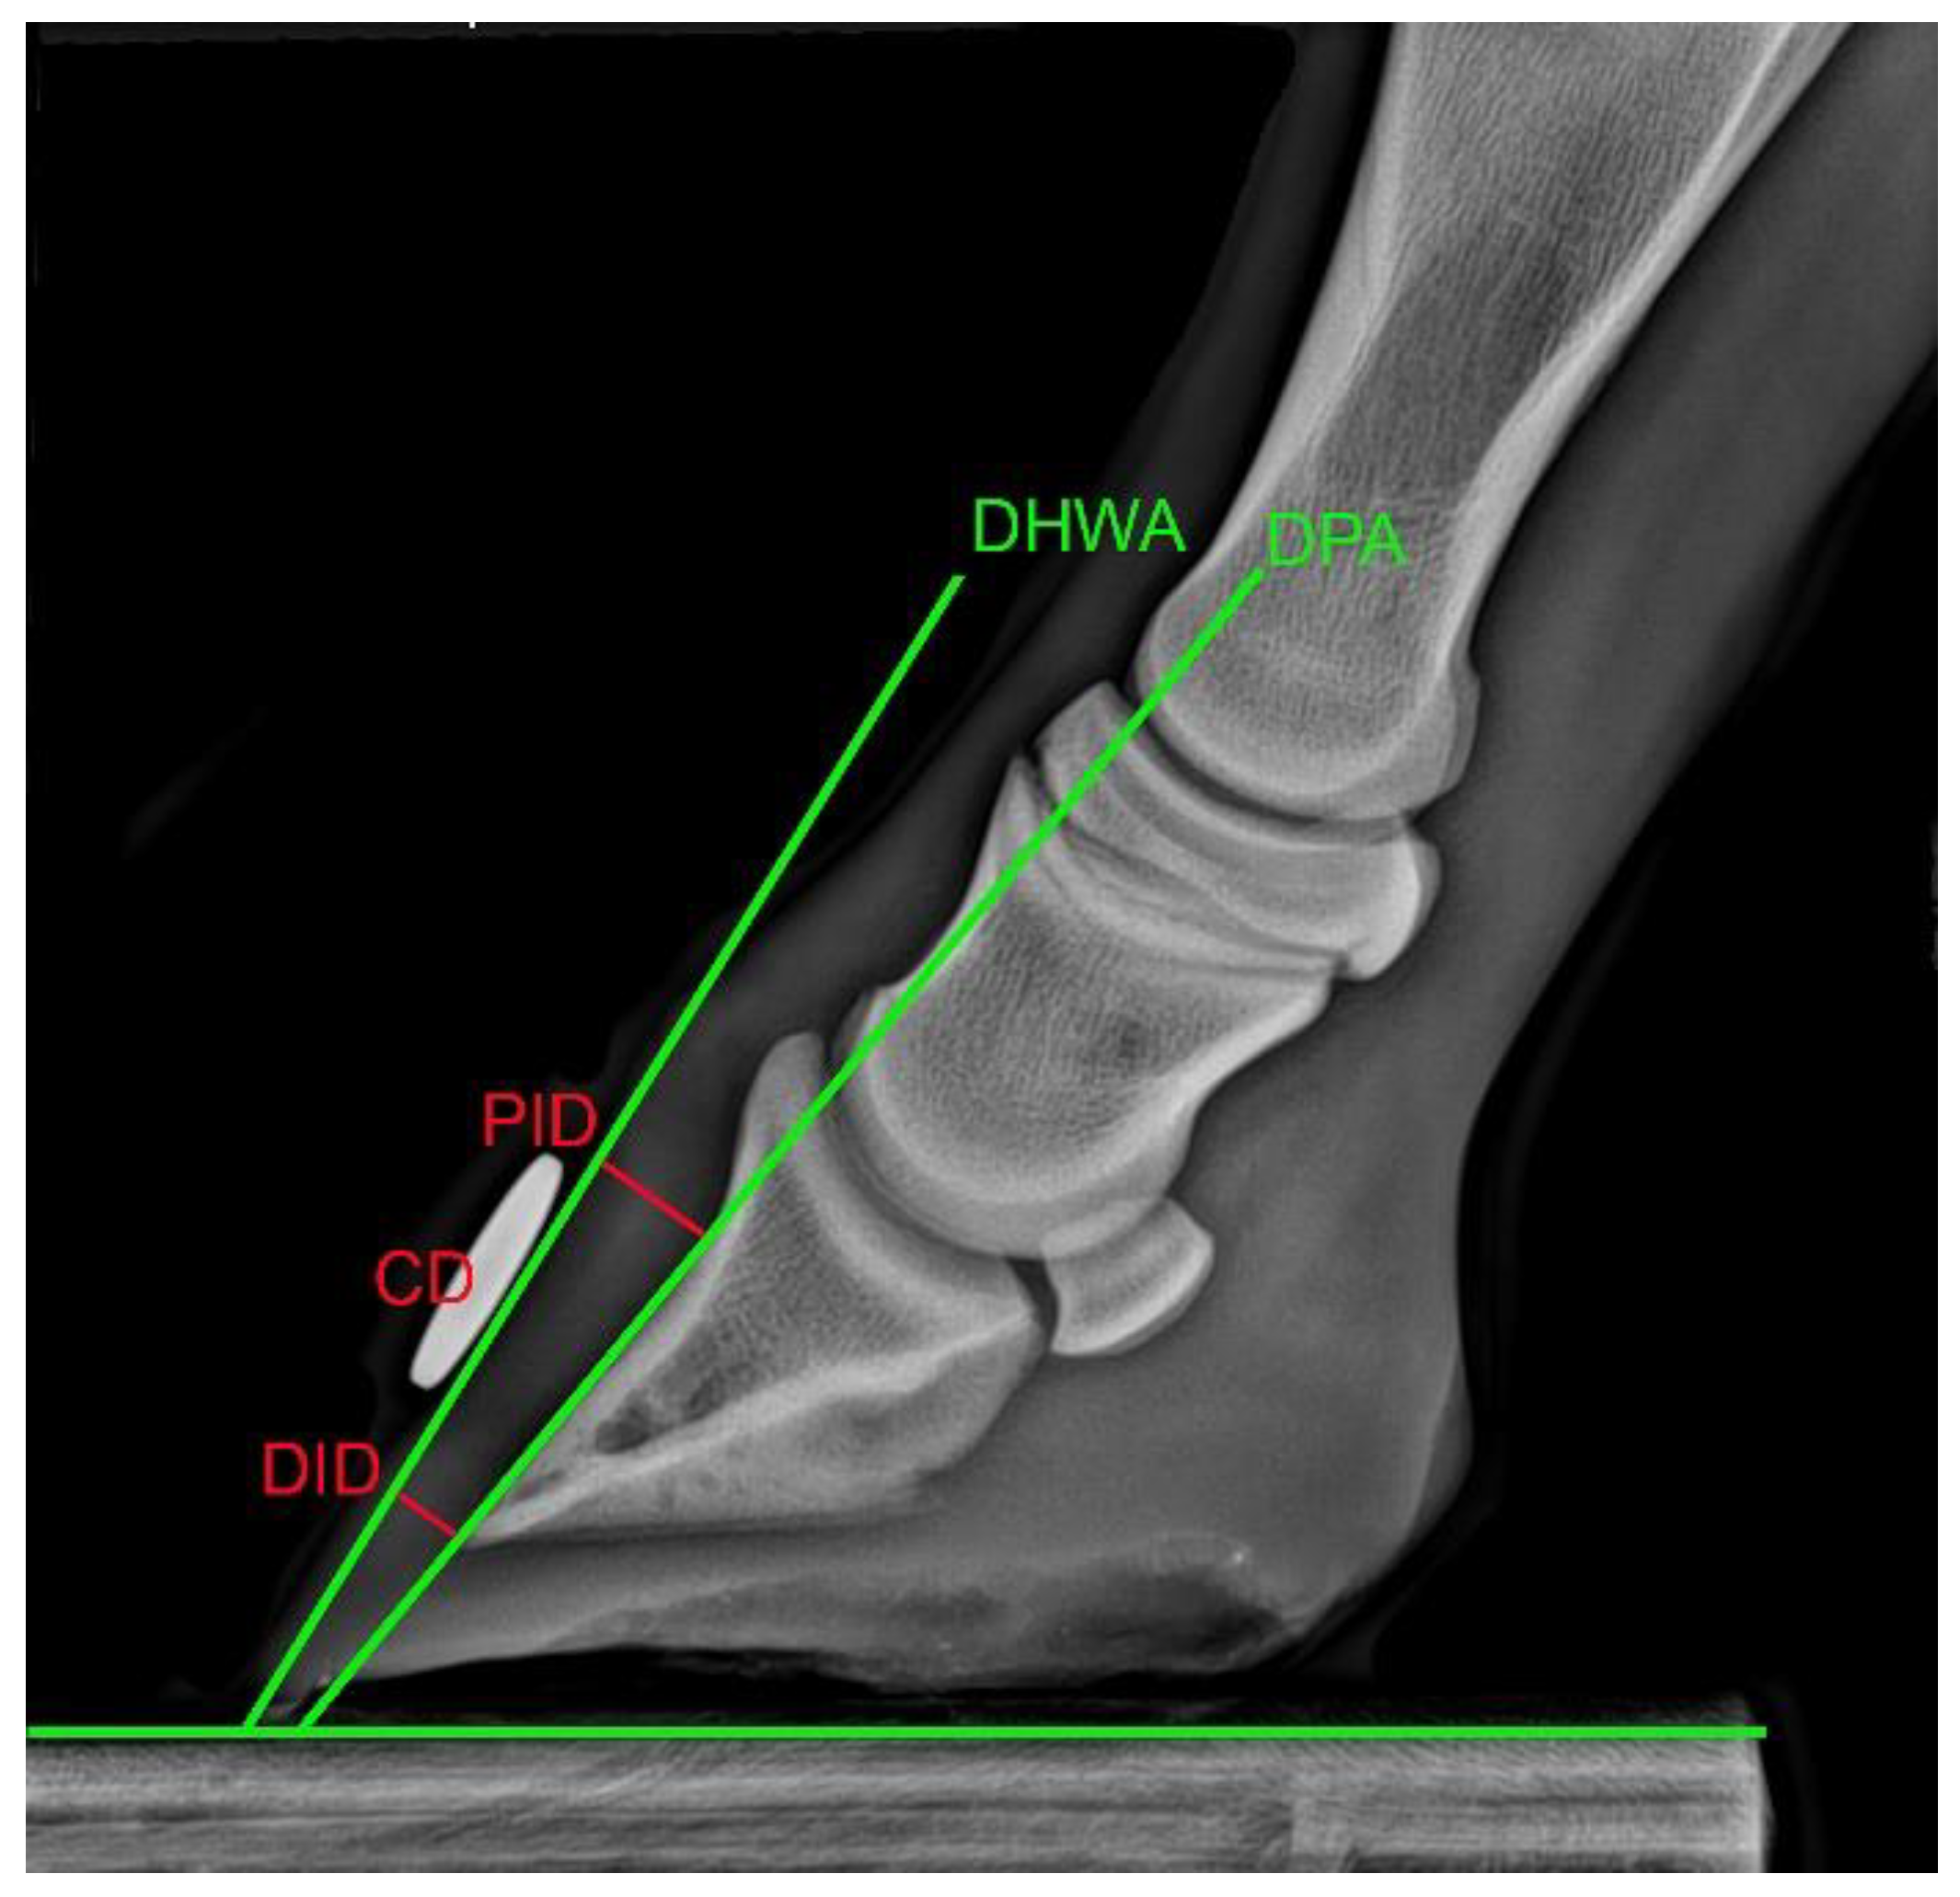

2.2. Measurement of Skeletal Conformational Features